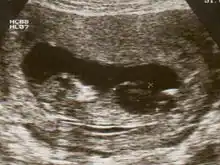

| Ultrasound of fetus with Down syndrome showing a large bladder | |

Fetal megacystis[1] is a rare disease that is identified by an abnormally large or distended bladder.

Fetal megacystis is diagnosed during pregnancy by ultrasound imaging procedures. Since it can be associated with genetic abnormalities, further ultrasounds and tests may be administered during pregnancy. It may also be diagnosed as megalocystis, and/or termed megabladder, which is the same condition.